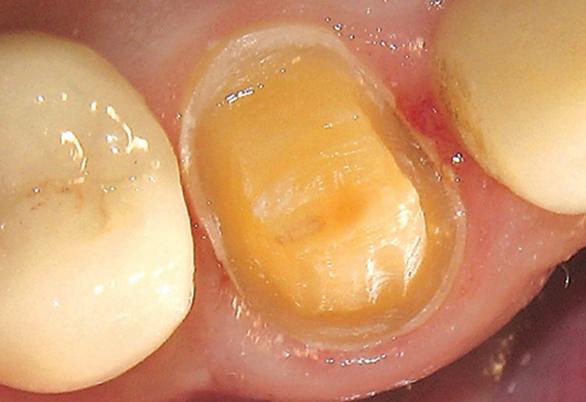

Clinical Case An 80-year-old male presented with a fractured and decalcified upper right canine (tooth #6). After reviewing clinical and radiographic findings it was determined that a full porcelain crown was the best treatment of choice. Initial impressions were obtained including a template for temporary fabrication, a study model and an opposing full arch mandibular impression (using 3M impression tray). After placing local anesthetic, the tooth was prepped for a full porcelain crown (Figure 1). Prior to the final impression, 3M retraction capsule (3M) paste was injected into the sulcus of tooth #6 (Figure 2). The retraction paste contains 15% aluminum chloride and is intended to provide temporary tissue retraction and enable a clean, dry and controlled sulcus. 3M retraction capsule paste material can be used alone or in conjunction with retraction cord. The soft and narrow tip of the 3M retraction capsule corresponds in size and shape to a periodontal probe; designed for direct placement in the sulcus (Figure 3).

Figure 1. Prepared tooth #6. Figure 2. 3M retraction paste in place around preparation. Figure 3. 3M™ Retraction Capsule and periodontal probe tips are similar in size.